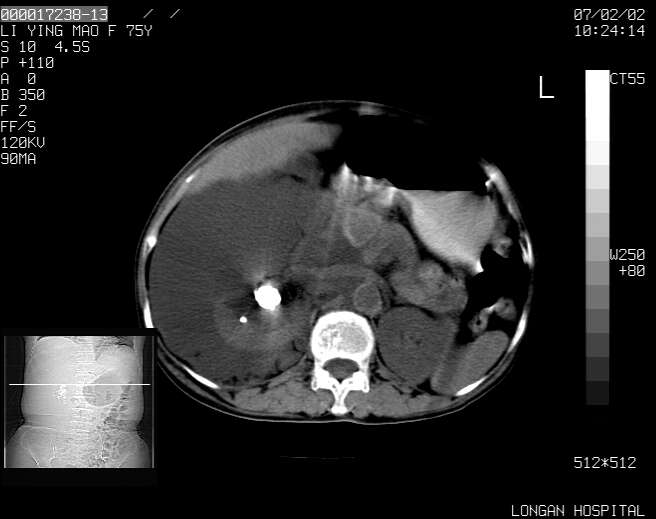

以下是引用dyqct在2007-2-10 8:53:00的发言:[br]考虑:1、肝脏多发囊肿[br] 2、左肾囊肿,右肾多发结石并积水。[br] 3、右胸少量积液。[br] 4、右肾周包裹性积液或淋巴管瘤(有见缝就钻的征象、薄隔、小结节状钙化)?[br] 5、腰椎动脉瘤样骨囊肿?[br] [br] [br]